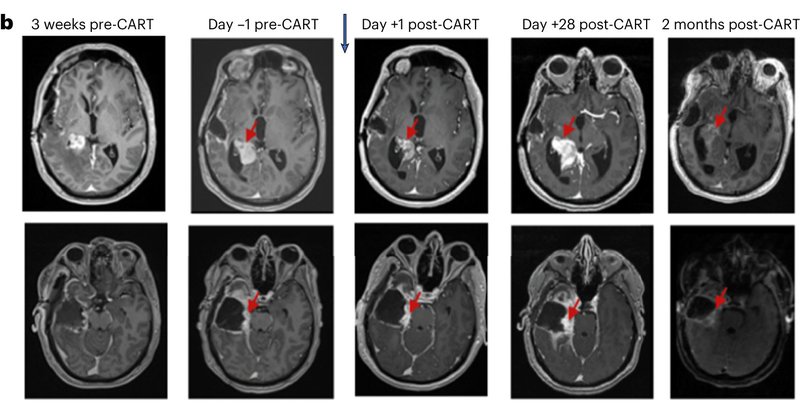

Our full P1 trial paper now available @NatureMedicine for treatment of recurrent #Glioblastoma completed at @PennMDForum @PennCancer with support from @KitePharma

#cureGBM We see anti tumor responses and have defined dose for ICV #CART cells

Excited to share our early phase 1 results for bivalent #CARTcells in recurrent #glioblastoma. Now online @NatureMedicine. Awesome team effort! @PennMedicine @PennCancer @PennNSG @DrORourke2

Nature Medicine - In an interim analysis of an ongoing phase 1 trial of CAR T cells targeting EGFR and IL13Ra2 in patients with multifocal, recurrent glioblastoma, intrathecal delivery is feasible...